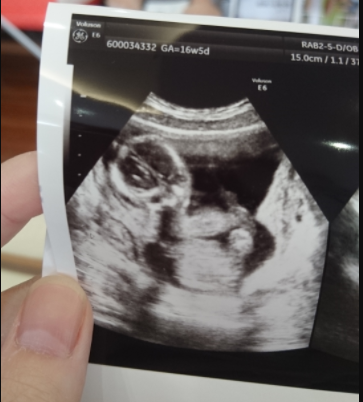

16週0日(16w0d・女の子)|ちーーさん さん(26歳)

エコー写真撮影時のエピソード:

なかなか顔を見せてくれず常に足か手で顔隠してたんですが、この時やっと顔見せてくれて主人とどっち似かね~って話したりしました。

義母は、「最近のエコー写真凄いね。昔は、はっきり分かりにくいしこんなのなかったよ」と4D写真にびっくりしてました。